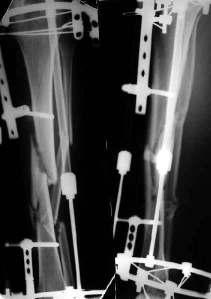

При невозможности или чрезмерной травматичности одномоментного восстановления длины можно пойти двухэтапно (аппарат, потом гвоздь). Похожий пример см. тут. Прошло уже года полтора после остеосинтеза. Может, коллега Зырянов покажет годичный результат, если есть?

Отправитель: Сергей Зырянов 16 Декабрь 2005, 08:20

Александр Николаевич, к сожалению больной не является на контрольные осмотры. Я последний раз видел больного, когда прошло 7 месяцев после операции БОС. У него все хорошо. Каких либо жалоб и ограничений в нагрузке нет. Высылаю снимки до операции и последние снимки.